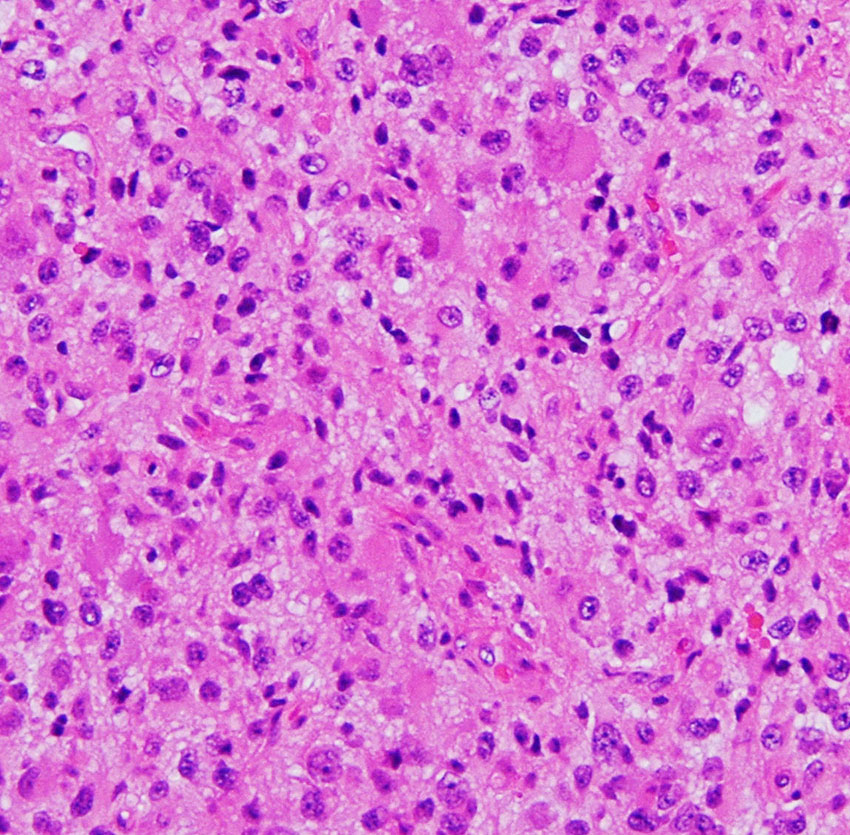

大小の神経細胞とグリア細胞が混在して存在します

小型のグリア細胞にも多少の異型があり腫瘍性グリアと考えられます

グレード1のgangliogliomaです

大脳皮質に大型の核を有する円形の神経細胞が散在しています。神経細胞間にグリア細胞がありますが腫瘍性増殖を示しません。MIB-1は1%以下でした。血管周囲にリンパ球浸潤があります。